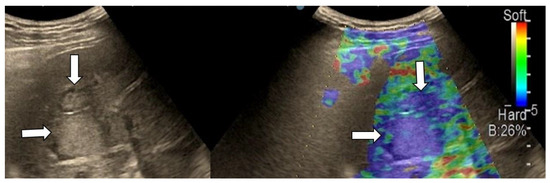

3.4. Real-Time Tissue Elastography

| Elasticity Type | Color Code |

|---|---|

| Type “a” | Homogenously green |

| Type “b” | Mosaic pattern with dominant green areas |

| Type “c” | Mosaic pattern with dominant blue areas |

| Type “d” | Homogenously light blue |

| Type “e” | Homogenously dark blue |